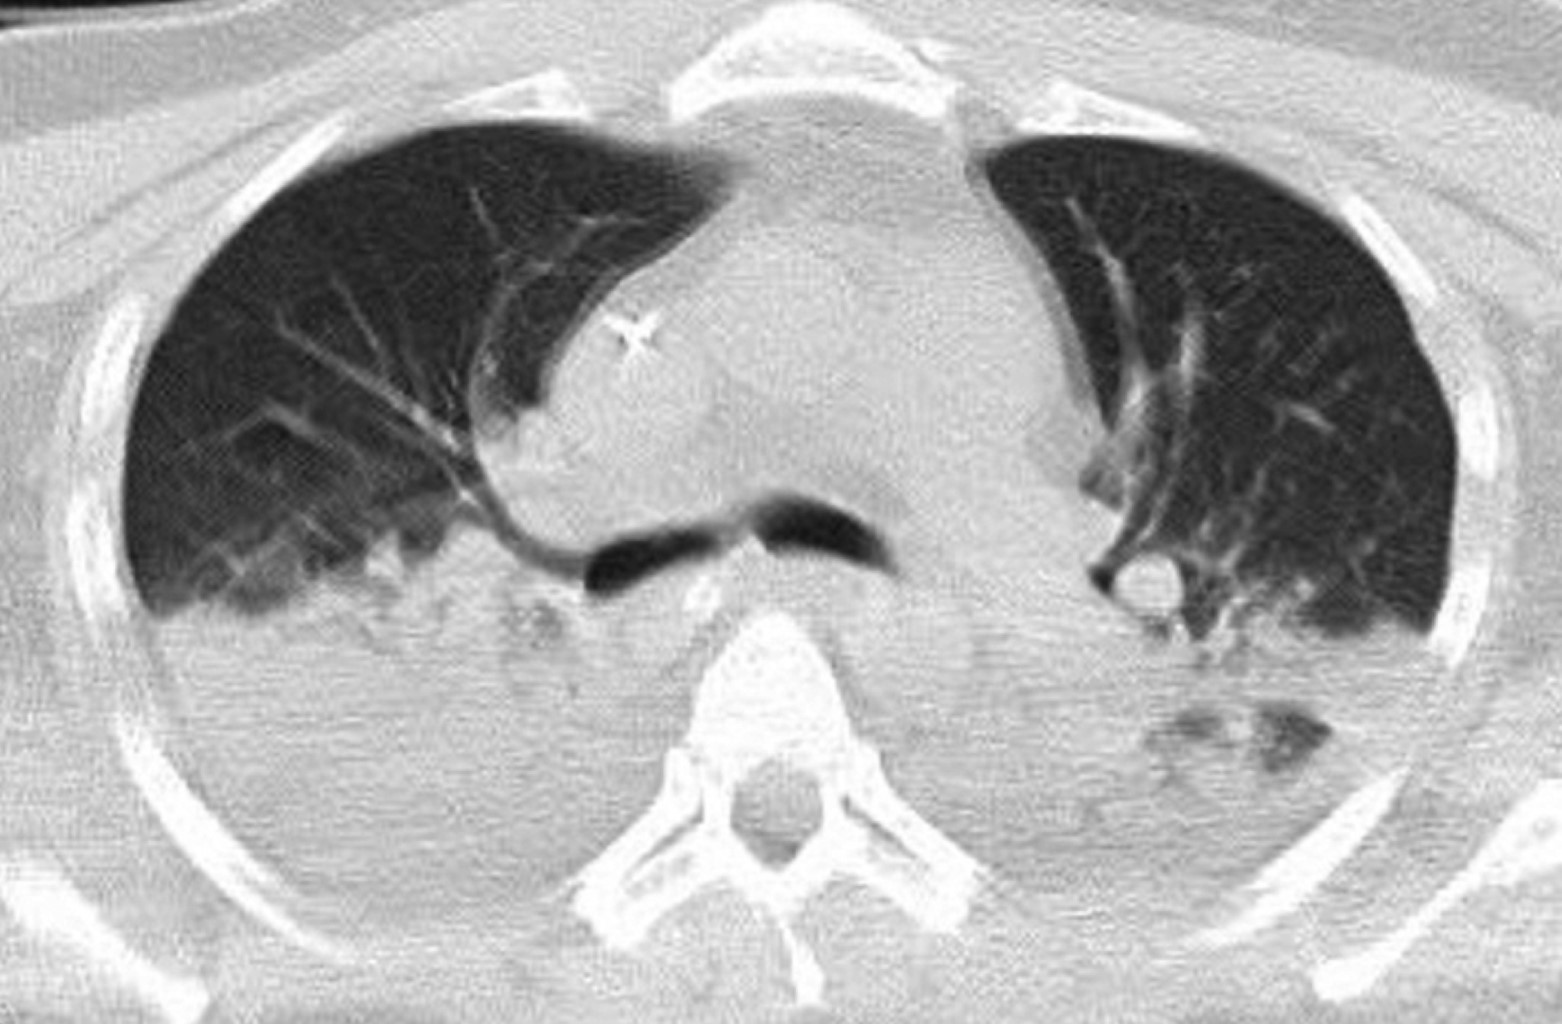

Coccidioidomycosis in a renal transplant immunosuppressed patient. A case report

Coccidioidomycosis is a systemic infection caused by dysmorphic fungi, Coccidioides immitis or Coccidioides posadasii, also known as desert rheumatism or valley fever, associated with arid and semi-arid climates. We present the clinical case of a 44-year-old male patient with renal transplant of 11 years of evolution under immunosuppressive treatment with atypical presentation of sepsis and development of acute respiratory distress syndrome secondary to lobar pneumonia due to Coccidioides immitis. The most common tomographic findings in this pathology include nodules, consolidations, pleural effusion, cavitations, etc., which were present in this patient.

Figure 1

Figure 2

Figure 3